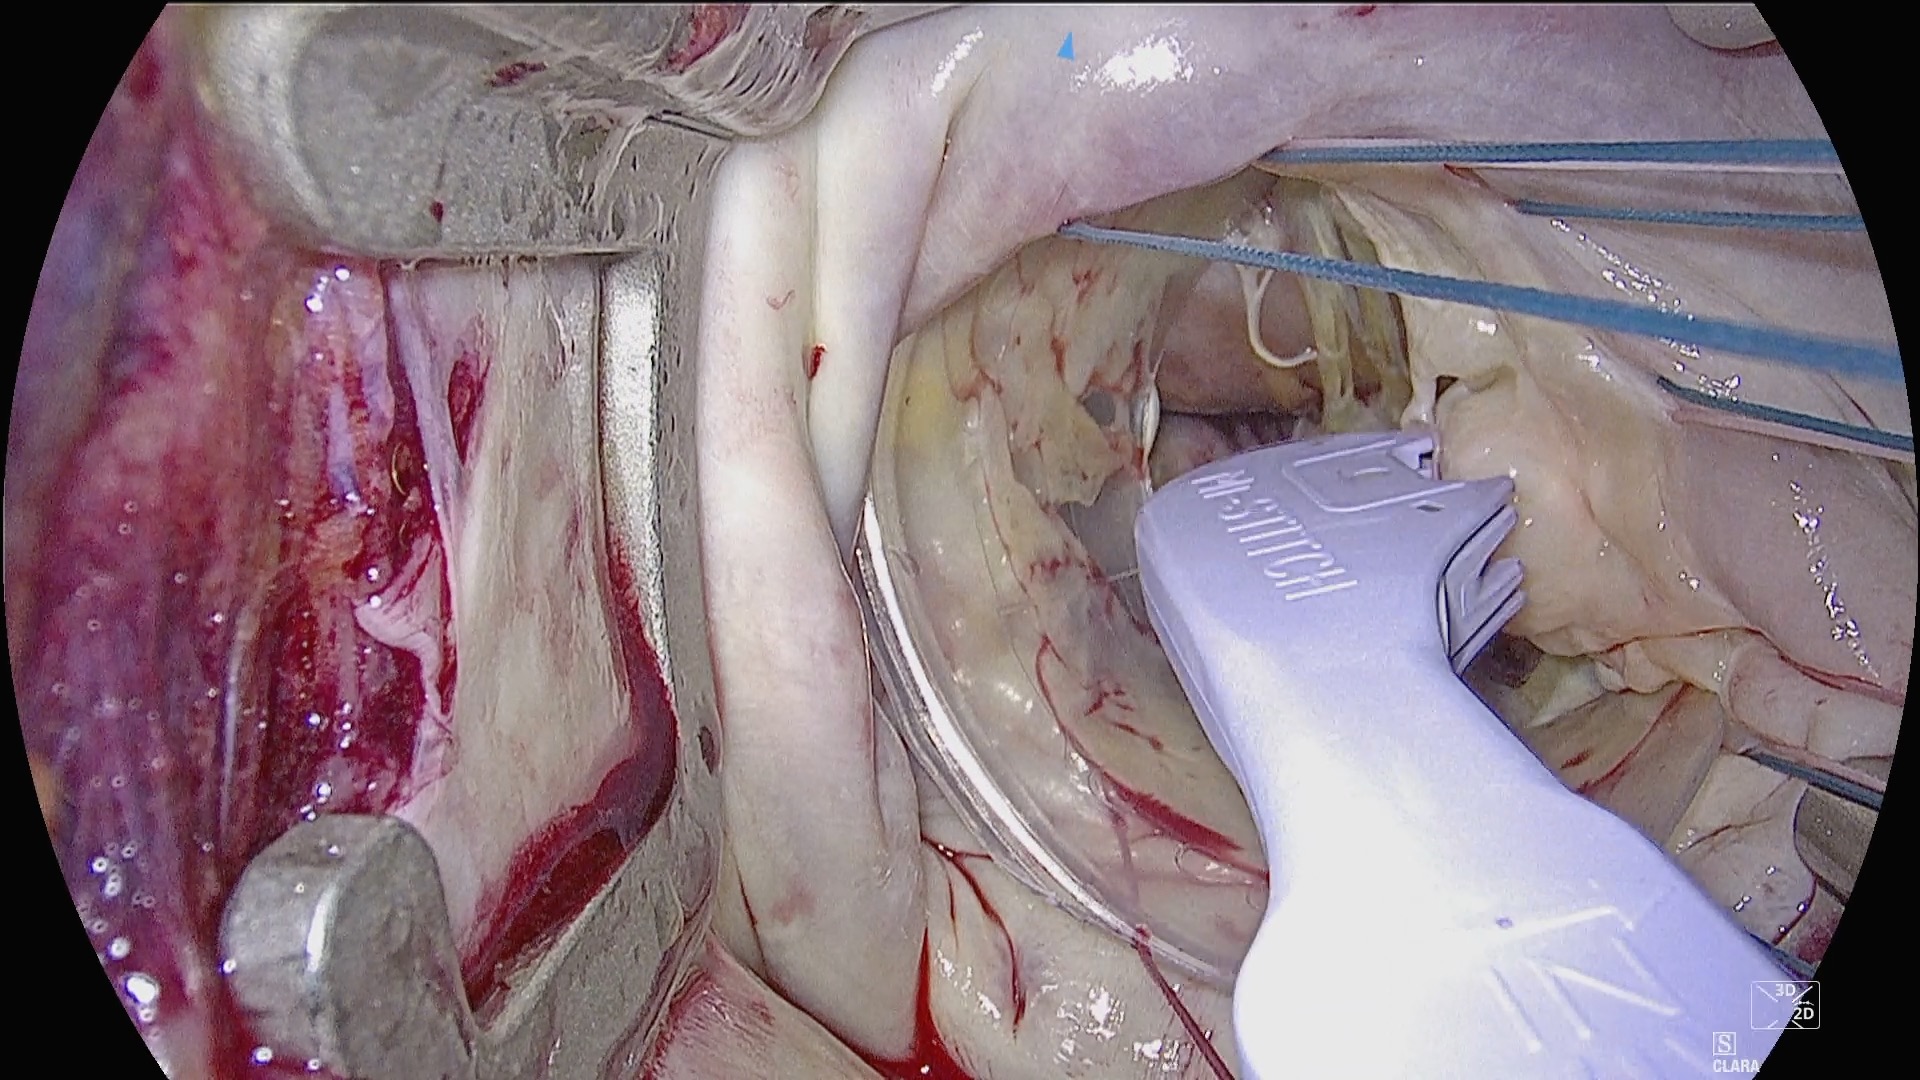

Mounted sterile directly to the table rails over the drape, the multiSTATION® System provides a modular, readily adjustable platform for holding the endoscope and other surgical instruments during the procedure. A custom left atrial retractor provides optimized exposure without the need for an additional incision.